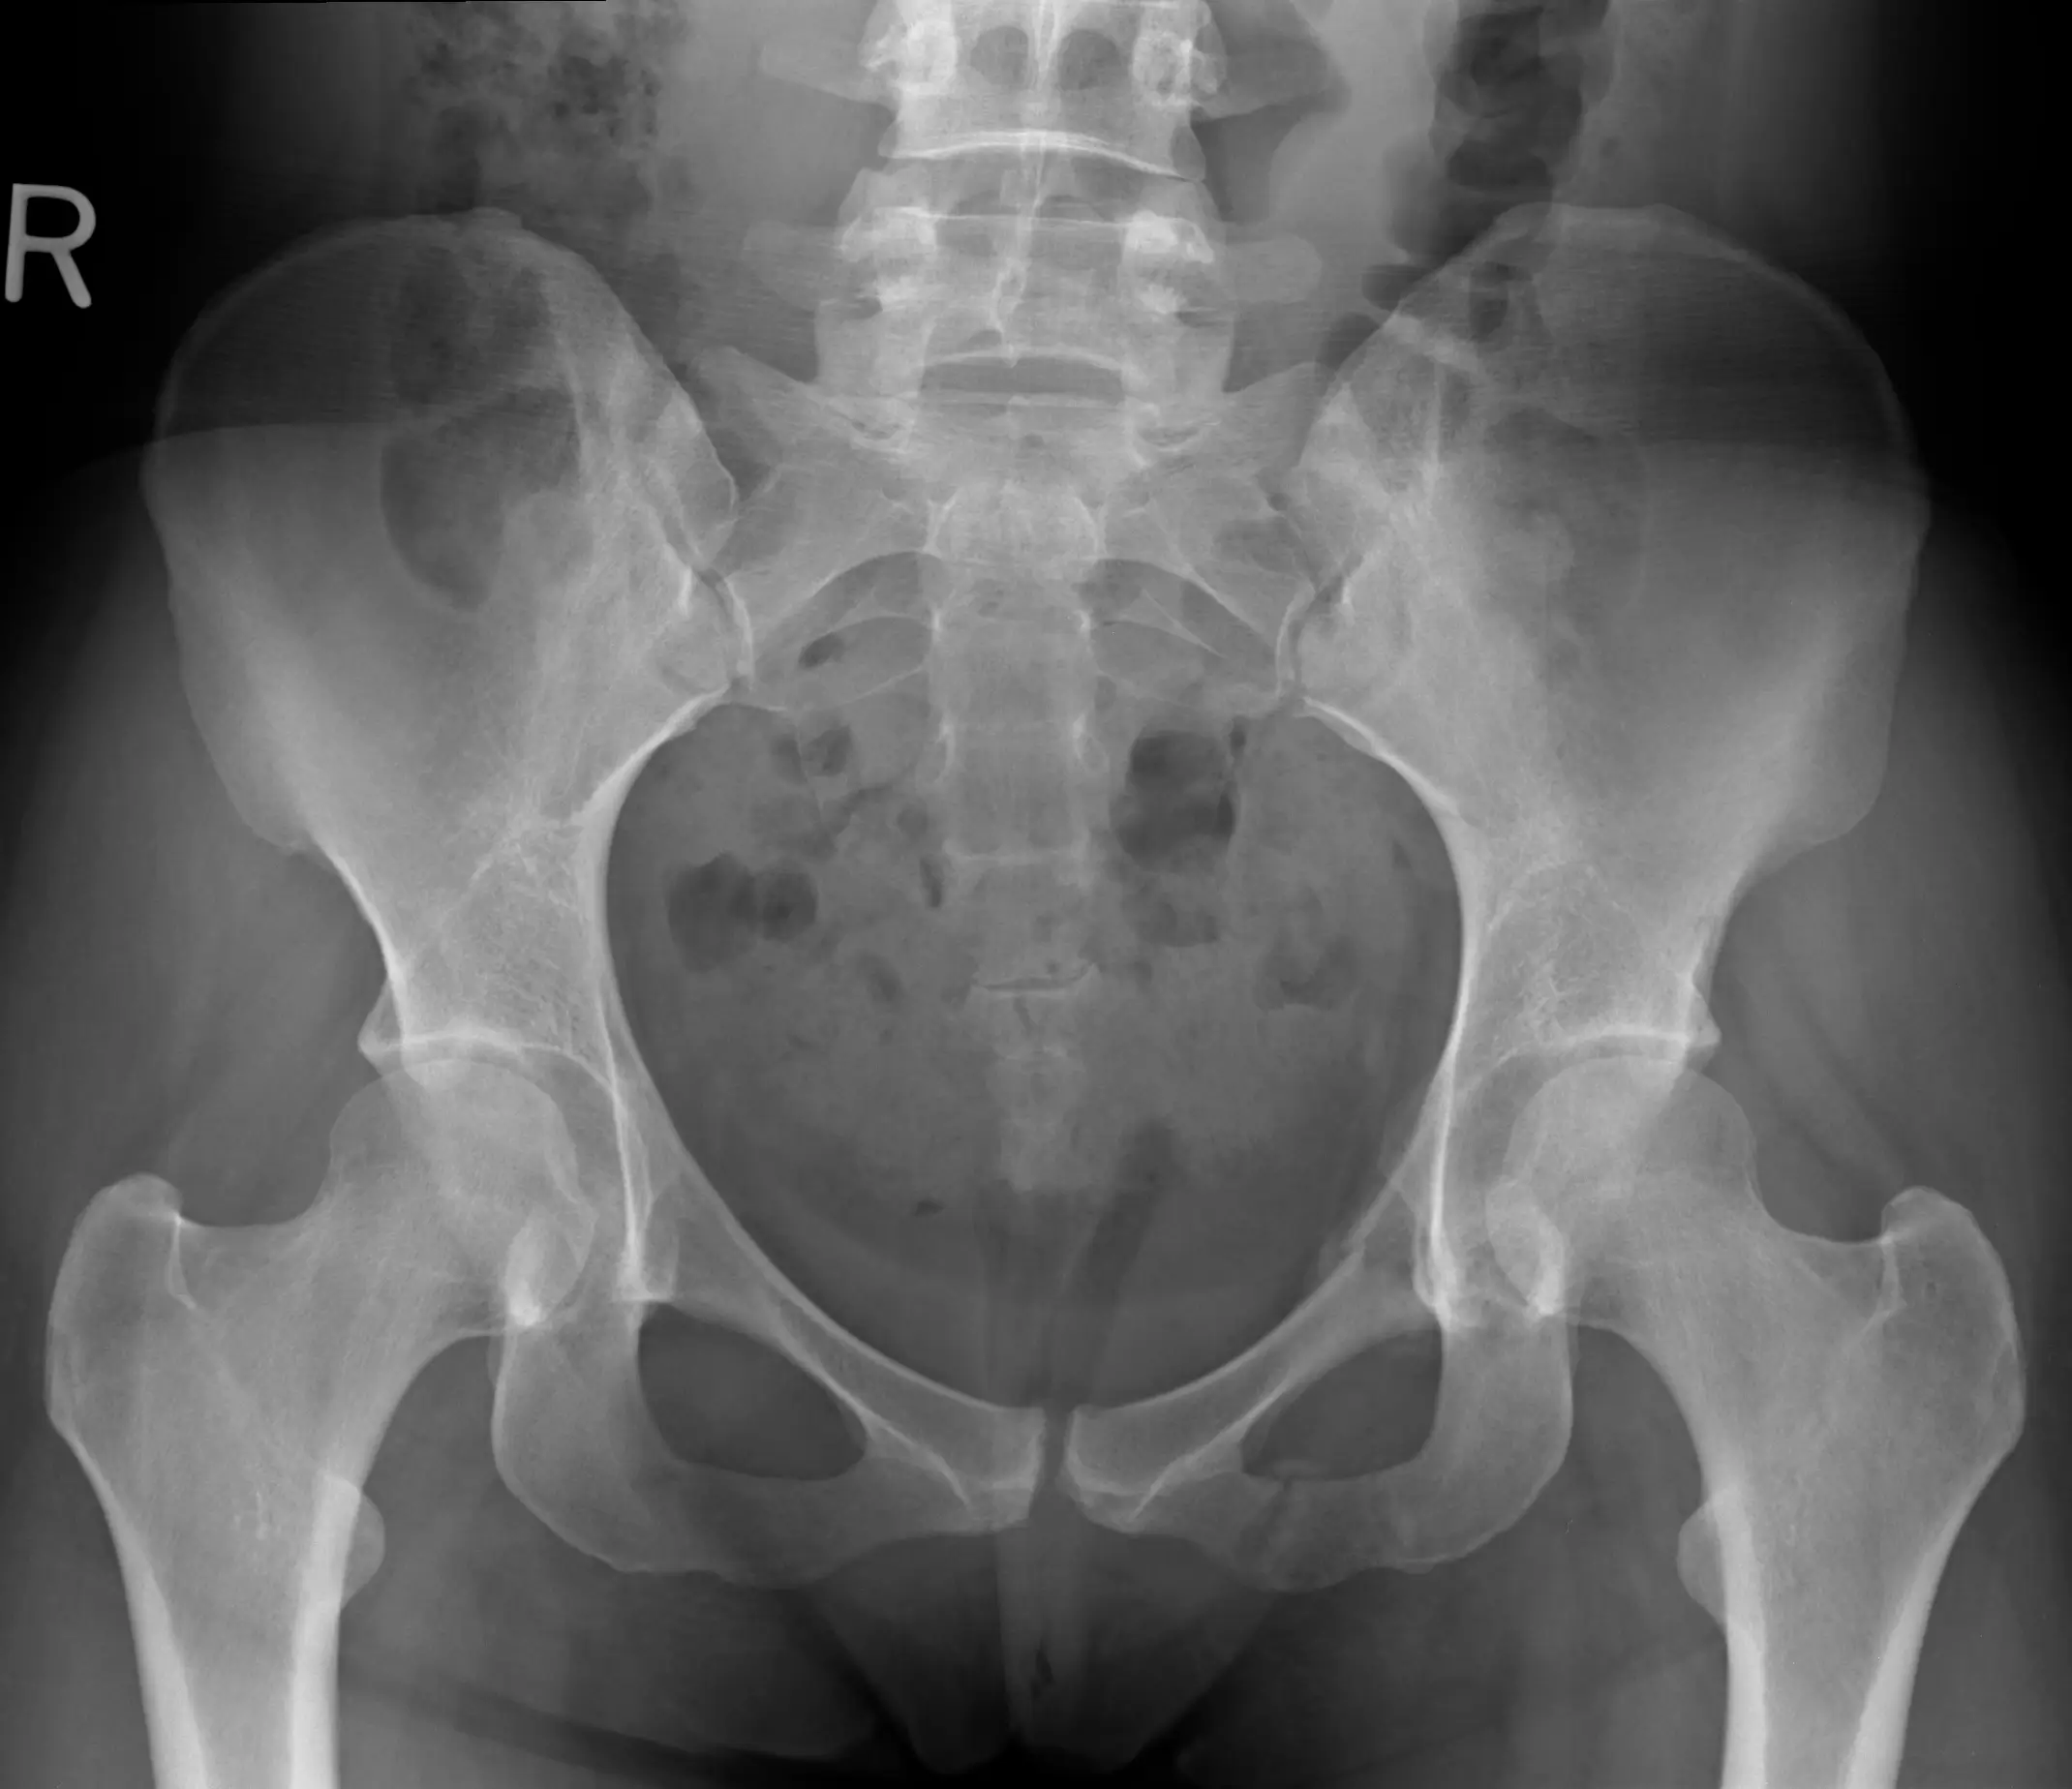

- Imagerie radiologique : mesure de l’angle de Cobb pour évaluer la gravité de la courbure et déceler les signes dégénératifs ou toute autre anomalie structurelle

Diagnostic et évaluation clinique

Le diagnostic repose sur une approche complète et intégrative, permettant de cerner l’étendue de la déformation et ses impacts :